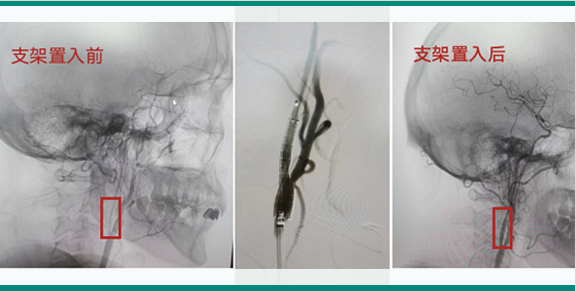

颅内狭窄的球囊扩张和支架置入术